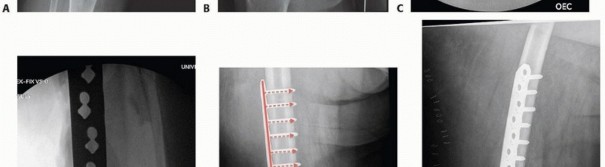

### TECH FIG 2 • AP radiograph (A) and scanogram (B) showing that length was reestablished with the external fixator. The rotation should be checked once again before locking the external fixator construct, as described earlier under Positioning. The same technique should be performed under sterile conditions. Varus-valgus alignment should be assessed before final tightening as well. This can be done by using the Bovie cord intraoperatively and assessing the mechanical axis of the limb by fluoroscopically evaluating from the hip to the ankle with the cord centered at the femoral head all the way to the ankle. The point at which the cord crosses the knee allows one to judge the varus-valgus alignment. 2. ## Open Reduction and Internal Fixation of the Distal Femur with Locking Plates (Type C Fractures) This technique can be used regardless of the locking plate system used. Each system's technique guide should be reviewed before use as each system has its own idiosyncrasies. Variations in plate application as well as reduction tools and techniques are unique to each system. The temporary external fixator is prepared using a “doubledouble” technique. The fixator is first prepared with a Betadine “scrub” (7.5% povidone-iodine) solution followed by a Betadine “paint” (10% povidone-iodine) solution (Beta-Beta preparation), followed by the extremity with a second Beta-Beta preparation. The surgeon then does an alcohol preparation, followed by iodine for the fixator, followed by alcohol and iodine on the skin. This has been successful in our practice and allows for maintenance of traction during the preparation and aids in the actual surgery, functioning as a femoral distractor. (Chlorhexidine is used in iodine- allergic patients.) An alternative is to completely remove the fixator components, except the pins, and wash, sterilize, and then reassemble the fixator on the patient after the leg has been prepared. If there is no temporary bridging external fixator, the metaphyseal component of the fracture can be reduced and brought out to length with a femoral distractor, a temporary simple external fixator, or manual traction if adequate help is available. Rotation of the proximal segment can be manipulated with the device used. 480 ### Midline Approach with an Extended Lateral Parapatellar Arthrotomy A straight incision is made directly anterior about 5 cm proximal to the superior pole of the patella and distally to the level of the tibia tubercle ( TECH FIG 3A). The lateral skin flap is developed to allow for a lateral parapatellar arthrotomy ( TECH FIG 3B). The arthrotomy is performed, ensuring a cuff of tissue on the lateral aspect of the patella for repair as well as medially on the quadriceps ( TECH FIG 3C). The patella can be subluxed medially or inverted with knee flexion to allow exposure of the condyles ( TECH FIG 3D). Additionally, a blunt Hohmann retractor can be placed on the medial side at the level of the condyle to retract the patella. The capsule is subperiosteally elevated off the lateral femoral condyle to allow for placement of the plate. The lateral collateral ligament is preserved because the dissection is limited to the anterior two-thirds of the lateral femoral condyle and plate placement is usually proximal to the lateral epicondyle. The medial side in the metaphyseal region is left undisturbed as much as possible.

TECH FIG 3 • Patient with grade II open distal femur fracture (also shown in FIGS 5D-F, 6B, and 7). A. Straight midline incision. B. Lateral skin flap is developed. C. Arthrotomy is started and then extended proximally into the quad tendon (dashed line). D. The arthrotomy is completed and the condyles are visualized with medial subluxation of the patella. ### Reduction of the Articular Surface The joint is evaluated to determine comminution. Joint reconstruction is then performed with direct reduction. Each condyle is fully assessed first for smaller fracture fragments, with the goal of restoring each condyle anatomically. Small-diameter screws ( <3.0 mm) may be used and can be countersunk underneath the articular surface. Large coronal fracture fragments are best treated with countersunk 3.5- to 4.5-mm lag-type screws. We use headless screws. Once each condyle is thought to be restored, or if a simple fracture pattern is present, the condyles should be reduced to each other using a large, pointed reduction forceps ( TECH FIG 4A-C). Each fragment can be rotated relative to another; this must be addressed as discussed before. The best way to assess this is under direct visualization and evaluating the reduction at the trochlear region of the patellofemoral joint. Additionally, preoperative evaluation assessing the lateral radiograph can guide the surgeon. Intraoperative fluoroscopy to reassess the lateral view is also useful. Temporary Kirschner wires or the guide pins for the locking screws for the plate can be used for additional stabilization of the two condyles ( TECH FIG 4D). 481

### TECH FIG 4 • The condyles are reduced under direct visualization (A) and confirmed with AP (B) and lateral (C) intraoperative fluoroscopic images. D. Guide pins through the plate template or screw trajectory guide are used to temporarily stabilize the intercondylar split. - Definitive Fixation of the Condyles This can be accomplished outside the plate first and supplemented with screws through the plate. The area around the proposed plate, the “periphery,” can be used for the screw placement to avoid interference with the plate placement itself. If this is done, then the metaphyseal fracture does not necessarily have to be properly reduced before initial screw placement. Screws can also be placed from medial to lateral to avoid interference with the plate. Definitive fixation can be accomplished through the plate also (see next section on Screw Placement). If this is done, the metaphyseal component should be reduced to ensure the proper flexion-extension alignment of the shaft with the condyles. This will ensure that the plate is collinear with the shaft once fixed to the distal segment. Otherwise, a malreduction in the sagittal plane will occur. The temporary Kirschner wires can be left in place to stabilize the joint. ### Reduction of the Shaft to the Distal Segment Once the articular surface is temporarily stabilized or reduced, the reduction of the shaft to the distal segment should be performed before plate application. This can be temporarily stabilized with Kirschner wires or Steinmann pins. Alternatively, precisely placed bumps underneath the distal segment can be used to correct the extension of the distal segment and align it with the shaft. Adjustment or loosening of the temporary external fixator can aid in reduction if needed. The plate can then be placed submuscularly. ### Placement of the Plate Each fixed-angle plating system is designed to help reestablish the valgus alignment of the distal femur. The screws in the distal portion of the plate are designed to be parallel to the joint surface. Thus, the initial guidewires for these screws should be placed parallel and confirmed by fluoroscopy. A distal “joint wire” can be placed to better evaluate this ( TECH FIG 5A). Placing the distal screws parallel to the joint will help ensure that when the shaft is brought to the plate, the anatomic axis of the femur is restored. With the variable-angle locking plates, the same technique should be employed to ensure that the plate is applied in a way to restore the anatomic axis of the femur. A fixedangle central screw hole still exists in these plates to aid in plate application ( FIG 11C, parallel lines; FIG 11D, red arrow/red circle). A distal screw trajectory guide is provided for some systems ( TECH FIG 5B). This can be used to help ensure accurate placement of the plate distally, and initial guidewires can be placed through this. Once the wires are placed, the guide can be removed and replaced with the plate using the wires as a guide. However, the shaft portion of the plate requires submuscular insertion, and thus the plate cannot be brought to an appropriate position to allow this to occur. 482

### TECH FIG 5 • A. Distal reference pin is placed to ensure that the proximal pin is parallel to the joint. B. Clinical picture depicting the guide. C. Different patient showing the penetration of the medial side with the guidewires to allow plate placement. D,E. The plate is placed with additional guide pins in place. - F,G. Lateral intraoperative fluoroscopic images ensure proper plate placement on the femur before screw insertion. To solve this, the guidewires can be driven through the medial side of the knee, which is distal enough to be safe ( TECH FIG 5C). The plate can then be inserted submuscularly and the guidewires driven back through the plate laterally, thus aligning the plate to the distal segment and ensuring proper screw trajectory and plate placement ( TECH FIG 5D,E). A single guidewire in a central hole will still allow flexion-extension placement of the plate if this needs to be adjusted. After placing the initial guidewire parallel to the joint distally, and ensuring the fracture is reduced, the surgeon should obtain fluoroscopic visualization of the plate proximally on the shaft to ensure that the plate is on the bone ( TECH FIG 5F,G). To ensure placement of the plate on the bone both proximally and distally, it is best to stabilize the plate distally 483 (where exposure is) using a guidewire in the center hole. This allows for a pivot point around which the AP positioning of the plate can be manipulated for the shaft. Fluoroscopy to image the lateral is then used to ensure placement.